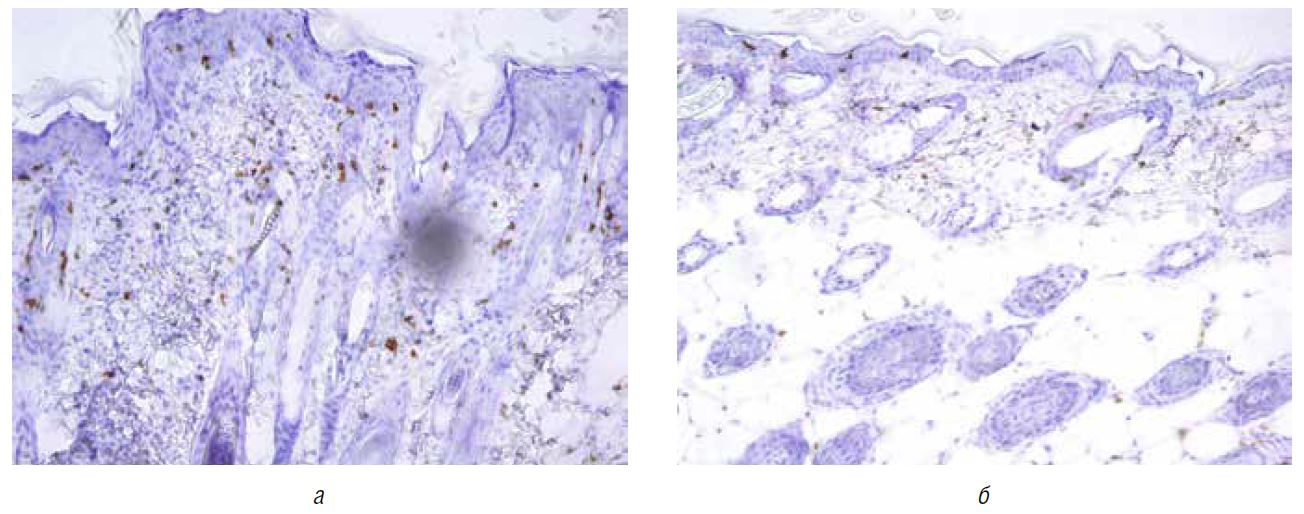

При иммуногистохимическом анализе проводили оценку площади экспрессии CD3+-клеток (маркер Т-лимфоцитов) и Ki67+-клеток (маркер пролиферации) (табл. 3). Установлено, что в группе I (имиквимод) наблюдалось наиболее выраженное количество CD3+-клеток.

На фоне проводимой терапии отмечалось уменьшение количества CD3+-клеток в коже: наименьшее количество обнаружено в группе IV (бетаметазона дипропионат), далее — в нарастающем порядке: в группе II (цинк пиритион активированный) и группе III (пиритион цинка) (рис. 3). Выявлено, что уровень пролиферативной активности клеток кожи в группах, где применяли препараты (II, III, IV), значительно ниже, чем в группах без терапии (I, V) (рис. 4). При сравнении групп, получающих лечение, не обнаружено статистически значимых различий, но отмечено, что наиболее выраженное снижение пролиферативной активности наблюдалось в группе IV (бетаметазона дипропионат), затем — в группе II (цинк пиритион активированный) и наименьшее — в группе III (пиритион цинка) и V (наблюдение).

Рис. 3. Непрямое иммуногистохимическое исследование CD3+-клеток в коже на лабораторной модели псориаза до терапии (а), после терапии препаратом скин-кап (б)